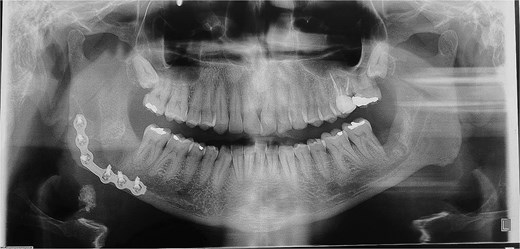

A 49-year-old male patient was referred, after a radiographic finding in a panoramic radiography, for evaluation of the lower right third molar (48) in an ectopic position associated with a radiolucent image, which suggested a cystic lesion (Fig. 1). A cone-beam computed tomography was made. The 3D imaging exams showed the presence of tooth 48 in the mandibular base, in the right angle region, associated with the radiolucent image, lingual fenestration, and intimate relationship between the third molar and the mandibular canal (Fig. 2). Due to the dental position, to have better visualization and less morbidity a submandibular extraoral approach was planned. The tooth removal and cyst curettage were made through the Risdon approach (Fig. 3). A fixation system with reconstruction plate (2.4 mm) was used to prevent a mandibular pathological fracture (Fig. 4). Anatomopathological examination of the cystic capsule was performed with a diagnosis of dentigerous cyst. In the postoperative period, the patient reported alteration in the sensitivity of the inferior alveolar nerve. Postoperative radiographic examinations showed adequate adaptation of the fixation system and complete surgical removal of the tooth and associated lesion. Orthopantomography with 4 months follow-up showed bone repair and adequate adaptation of the fixation system (Fig. 5).